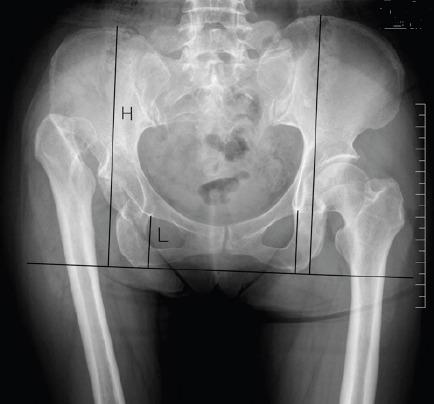

To investigate whether adult patients with unilateral developmental dysplasia of the hip (UDDH) have pelvic asymmetry and what correlation existing between them. Methods: A total of 100 adult patients with UDDH were enrolled in the retrospective observational study in Shanghai Jiaotong University Affiliated Sixth People's Hospital, Shanghai, China, between January 2012 and February 2014. The anteroposterior pelvic radiographs were reviewed and the pelvic heights and ischium heights were measured and compared between the affected and non-affected sides to find out the relationship between the pelvic morphology and hip dysplasia. Results: The pelvic heights demonstrated significant differences between the non-affected side and the affected side in patients with Crowe type II-IV UDDH (p less than 0.05), but not in patients with Crowe type I UDDH (p=0.09). There were significant differences in the bilateral ischium heights in patients with Crowe type III and IV UDDH (p less than 0.05), but not in patients with Crowe type I and II UDDH (p=0.78, p=0.055). In addition, the degree of hip dysplasia was positively associated with the degrees of asymmetry of pelvis (r=0.78, p less than 0.001) and ischium (r=0.72, p less than 0.001) in UDDH patients. Conclusion: The pelvic asymmetry exists in adult patients with UDDH. In addition, the degree of asymmetry has correlation with the degree of hip dysplasia. We recommend that it should be taken more cautions to use teardrops and ischial tuberosity as anatomy landmarks to balance leg-length discrepancy for unilateral DDH patients in preoperative planning and total hip arthroplasty.

探讨成年单侧发育性髋关节发育不良(UDDH)患者是否存在骨盆不对称及其之间的相关性。方法:2012年1月至2014年2月,在上海交通大学附属第六人民医院对100例成年UDDH患者进行回顾性观察研究。回顾骨盆前后位X线片,测量并比较患侧与非患侧的骨盆高度和坐骨高度,以了解骨盆形态与髋关节发育不良之间的关系。结果:Crowe II-IV型UDDH患者非患侧与患侧的骨盆高度存在显著差异(p<0.05),而Crowe I型UDDH患者无显著差异(p=0.09)。Crowe III型和IV型UDDH患者双侧坐骨高度存在显著差异(p<0.05),而Crowe I型和II型UDDH患者无显著差异(p=0.78,p=0.055)。此外,UDDH患者髋关节发育不良程度与骨盆不对称程度(r=0.78,p<0.001)和坐骨不对称程度(r=0.72,p<0.001)呈正相关。结论:成年UDDH患者存在骨盆不对称。此外,不对称程度与髋关节发育不良程度相关。我们建议,在术前规划和全髋关节置换术中,对于单侧DDH患者,以泪滴和坐骨结节作为解剖标志来平衡肢体长度差异时应更加谨慎。